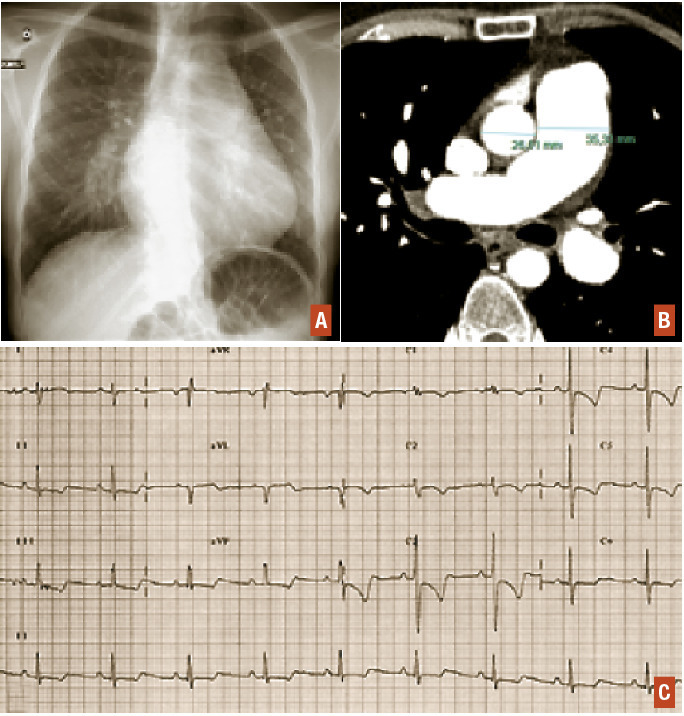

La radiographie de thorax retrouve le plus souvent une hypertrophie des artères pulmonaires associée à une cardiomégalie (augmentation de l’index cardiothoracique) (fig. 2A). La radiographie de thorax permet également de rechercher des éventuelles atteintes parenchymateuses associées orientant vers le groupe 3 (hypertension pulmonaire associée à une maladie respiratoire) ou de signes d’œdème pulmonaire orientant vers le groupe 2 (hypertension pulmonaire postcapillaire).

L’angioscanner thoracique permet également de mettre en évidence une hypertrophie des artères pulmonaires et des cavités droites (fig. 2B). Il est plus sensible que la radiographie de thorax pour rechercher des anomalies parenchymateuses associées ou des signes évocateurs de maladie veino-occlusive. Il a également un rôle important dans le bilan des hypertensions pulmonaires post-emboliques.

L’électrocardiogramme retrouve classiquement des signes d’hyper­trophie auriculaire et ventriculaire droite (fig. 2C).